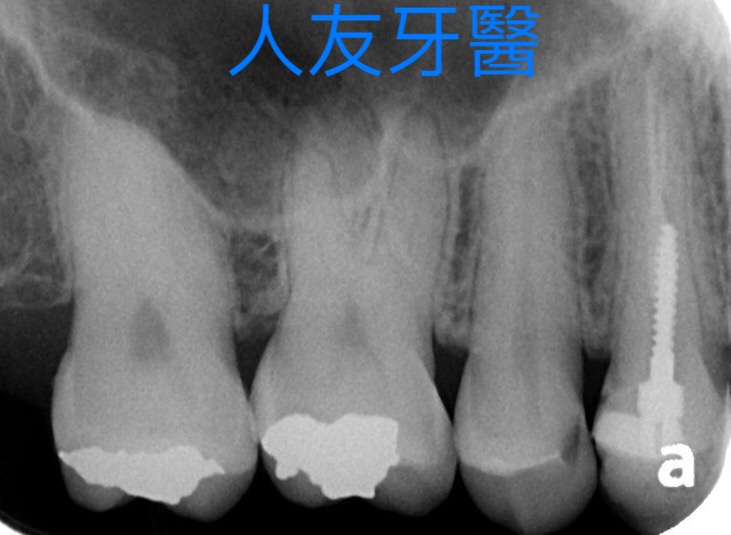

根管治療 Q & A